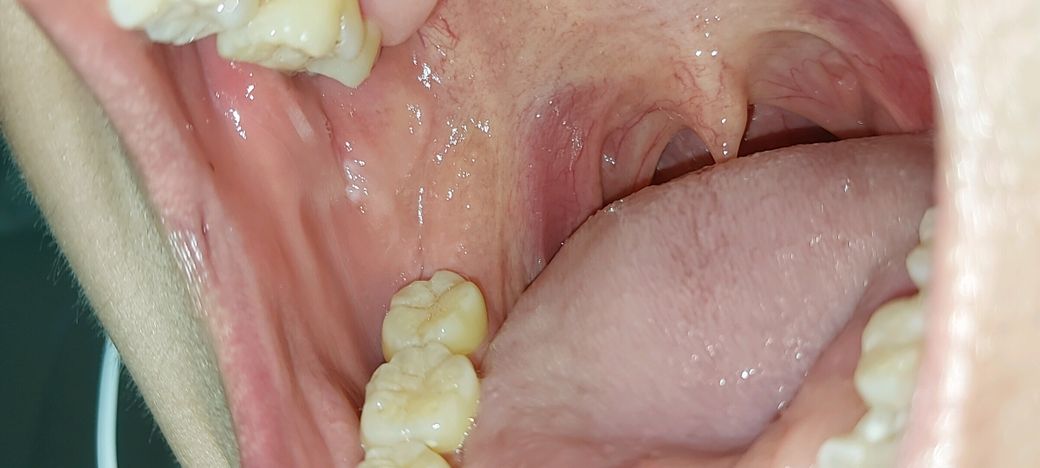

입안에 안아픈데 안낫는 흰점이 있습니다 이게 뭘까요..?

제가 한 한달전에 입안에 작은 흰점을 발굔했습니다. 근데 이게 3주정도 지나도 안나아서 이비인후과에 가서 여쭤봤더니 별거 아닌거 같다는 식으로 얘기하시고 무슴 박피? 소독? 같은거만 간단하게 해주시고 나왔습니다. 근데 이게 좀 더 커지고 옆에 한개가 더 생긴거 같아서 걱정되는 마음에 여쭤봅니다.. 통증은 없고 만져보면 까슬까슬한 느낌입니다.

저부위는 볼살이 치아에 계속 씹히면서 생기는 거 같습니다. 크게 아프거나 그렇지 않으면 문제가 잇는건 아닙니다.